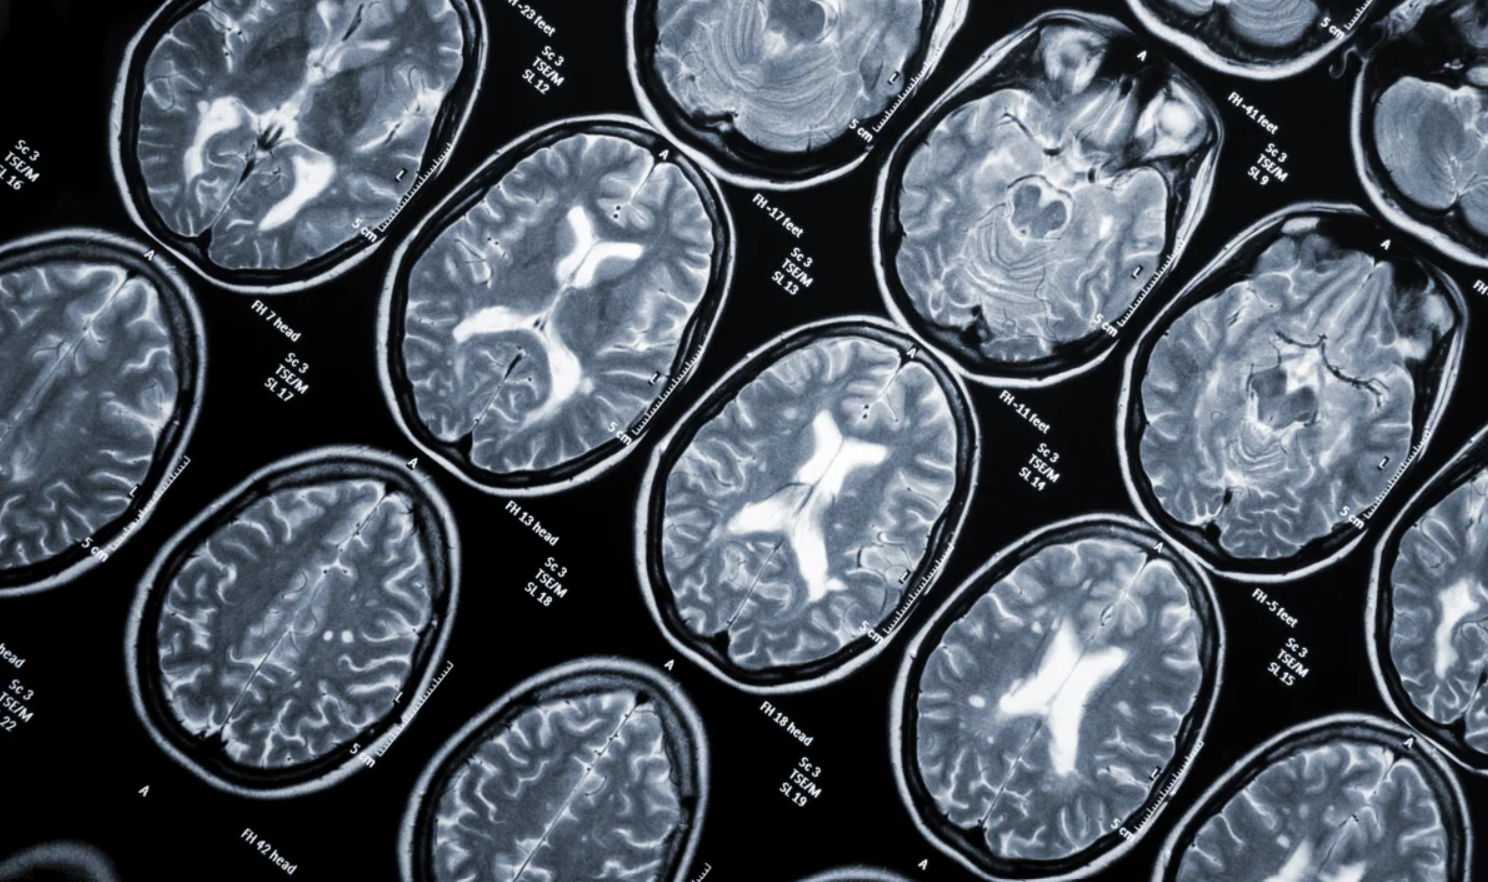

Πολλαπλή σκλήρυνση – Ποιος κοινός ιός μπορεί να την πυροδοτήσει – Ανησυχητική έρευνα

Το ανθρώπινο σώμα διαθέτει πολλές άμυνες για να προστατεύεται από ασθένειες και μολύνσεις. Ωστόσο,…